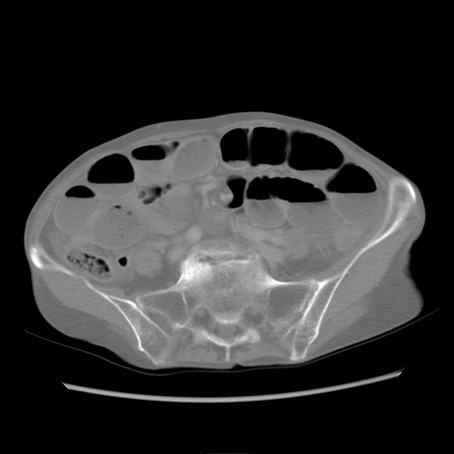

症例25(横断像)

【症例】80歳代女性

【主訴】胸のつかえ感

【現病歴】約9時間前に食後から胸のつかえた感じあり、嘔吐あり、来院。

【既往歴】胃癌(全摘)、胆摘、虫垂炎

【身体所見】心窩部に圧痛あり、反跳痛なし。

【データ】WBC 5700、CRP 0.05